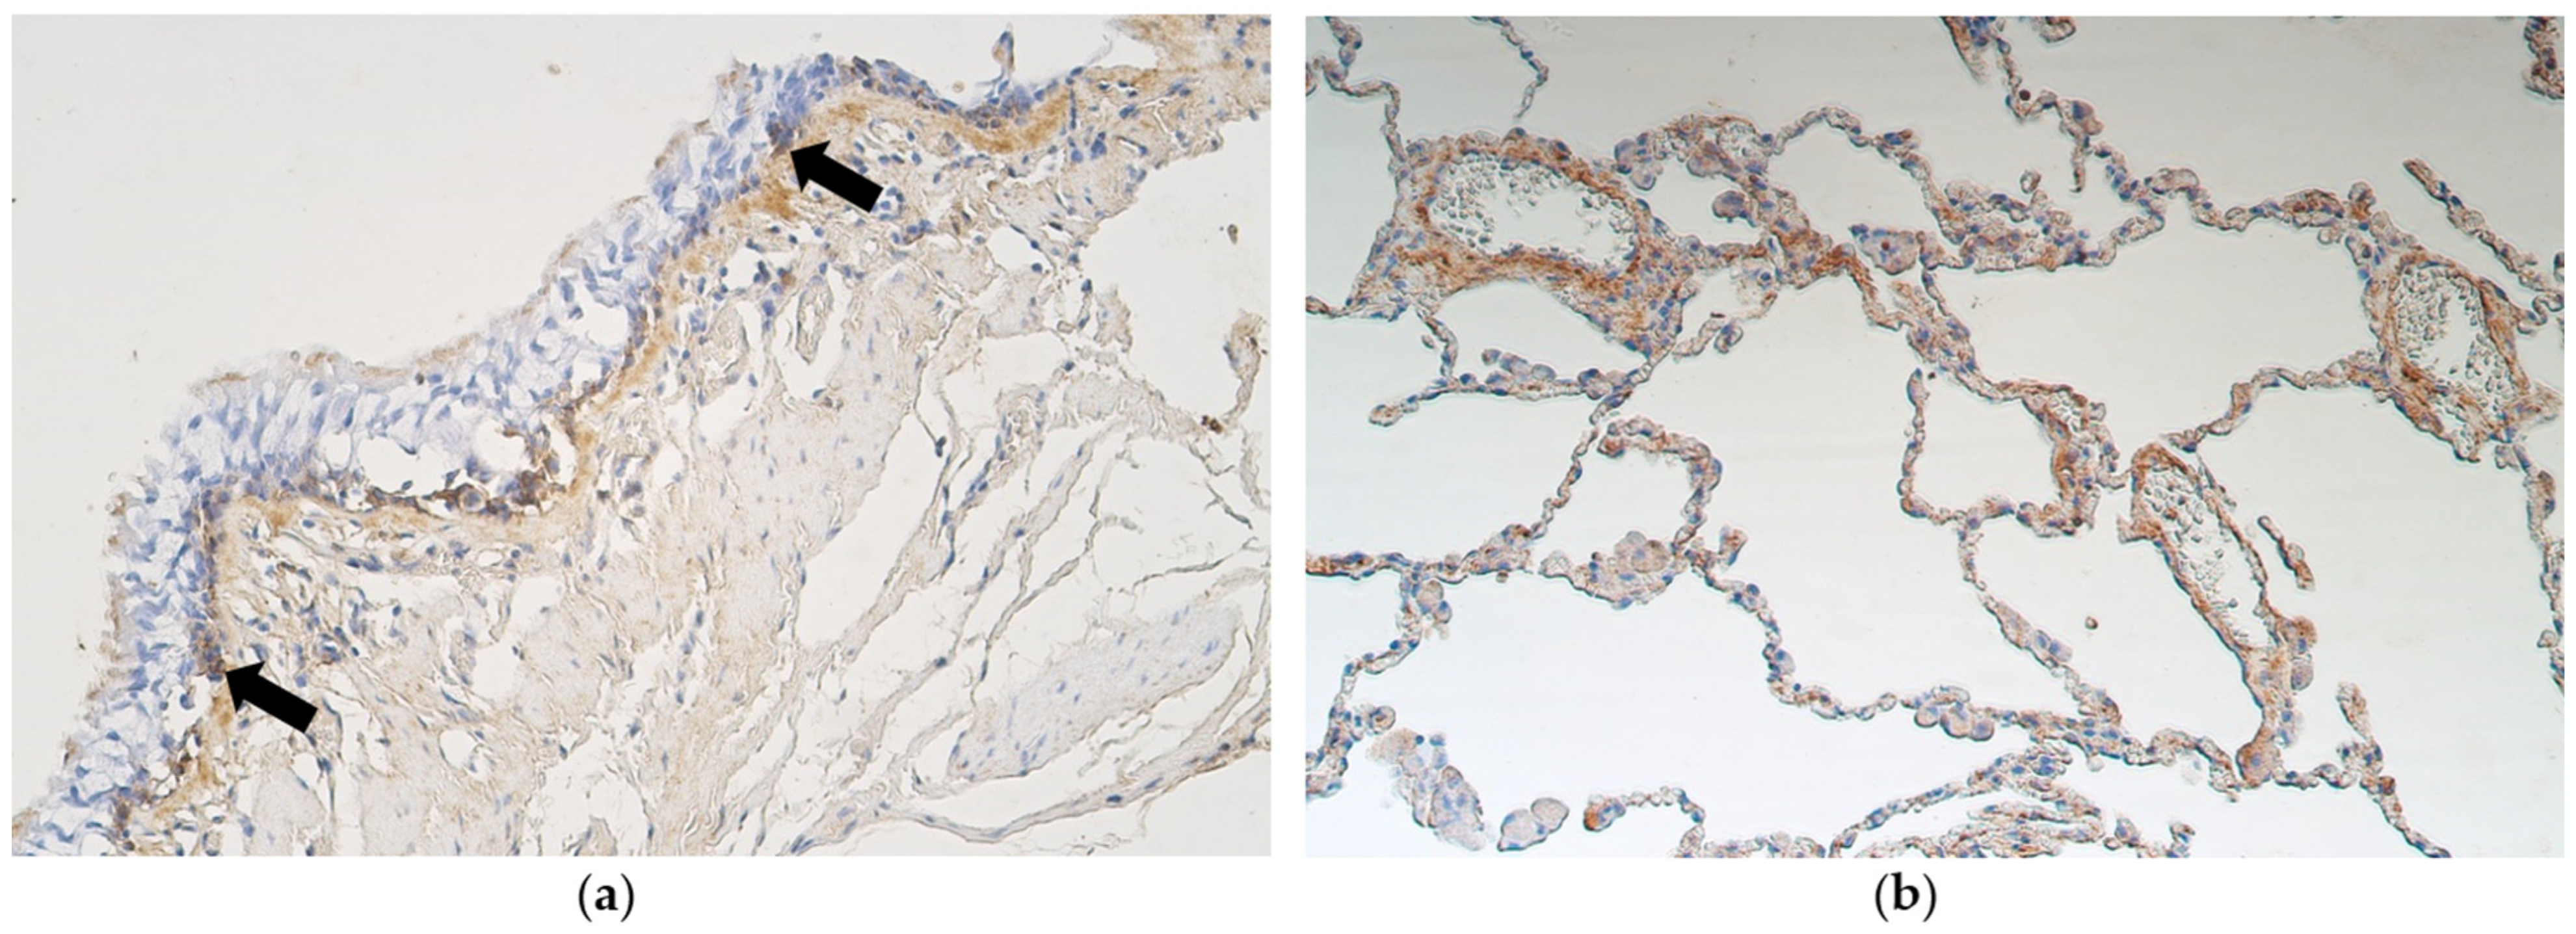

3.2. Immunohistochemistry

- A moderate number of nestin-positive cells in the alveolar epithelium and cartilage of bronchi with pseudostratified ciliated epithelium suggests a significant role of neuronal origin cells in these structures, to be intensified in metaplastic bronchial epithelium.

- A practically non-changed number of CD34-positive cells excludes any difference in stimulation of endothelial origin cells between lungs with different types of epithelium, while an increase in VEGF in structures with metaplastic epithelium suggests the presence/influence of tissue ischemia impact on possible development/maintenance of metaplasia.